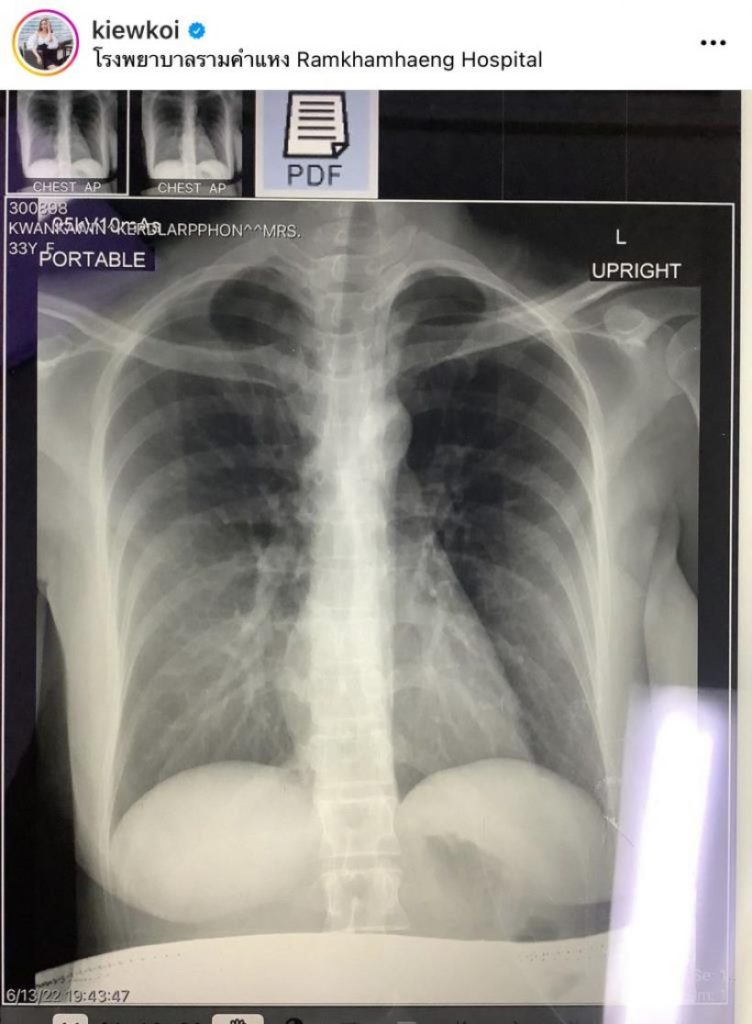

ส่วนพี่โย (Astra 2+ Pfizer 2) ไม่ไอเลย แต่มีไข้สูง ปวดตัว แน่นจมูก ปวดหัว รับยาต้านแล้ว วันนี้วันที่ 4 แล้ว อาการค่อยๆดีขึ้นตามลำดับ ปอดยังปกติดี แม่ท้องท่านอื่นที่ติดโควิท แม้ไม่ได้รับยาต้าน แต่คุณหมอแจ้งว่าไม่ต้องกังวล อาการจะค่อยๆ ดีขึ้นเอง เอกซเรย์ปอดได้ถ้าจำเป็น แต่ต้องมีแผ่นตะกั่วปิดท้องให้น้องด้วยนะคะ สงสารลูกจัง แม่ไอทีนึงสะเทือนทั้งตัว หลังจากนี้จะดูแลตัวเองให้ดีมากๆ ขอบคุณทุกกำลังใจนะคะ ขอบคุณรพ. รามคำแหงที่ดูแลดีมากๆ ค่ะ คุณหมอบอกว่าช่วงนี้กลับมาเป็นกันเยอะขึ้นมาก ดูแลตัวเองด้วยน้าาทุกคน